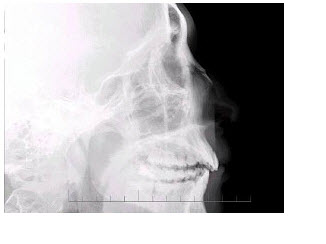

101、单项选择题

男,72岁,喉部异物感2~3天。体检:咽喉部慢性充血,结合图像,最可能的诊断为()

A.正常表现

B.会厌征

C.颈椎退变

D.食管型颈椎病

E.以上都不是